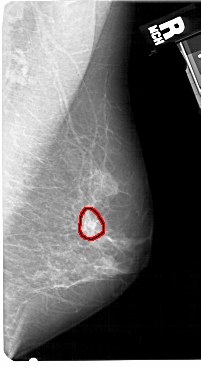

A_1520_1.RIGHT_CC

RIGHT_CC LINES 5491 PIXELS_PER_LINE 2641 BITS_PER_PIXEL 12 RESOLUTION 43.5 OVERLAY

FILE: A_1520_1.RIGHT_CC.OVERLAY

TOTAL_ABNORMALITIES 1

ABNORMALITY 1

LESION_TYPE CALCIFICATION TYPE PLEOMORPHIC DISTRIBUTION CLUSTERED

LESION_TYPE MASS SHAPE IRREGULAR MARGINS SPICULATED

ASSESSMENT 4

SUBTLETY 3

PATHOLOGY MALIGNANT

TOTAL_OUTLINES 1

BOUNDARY